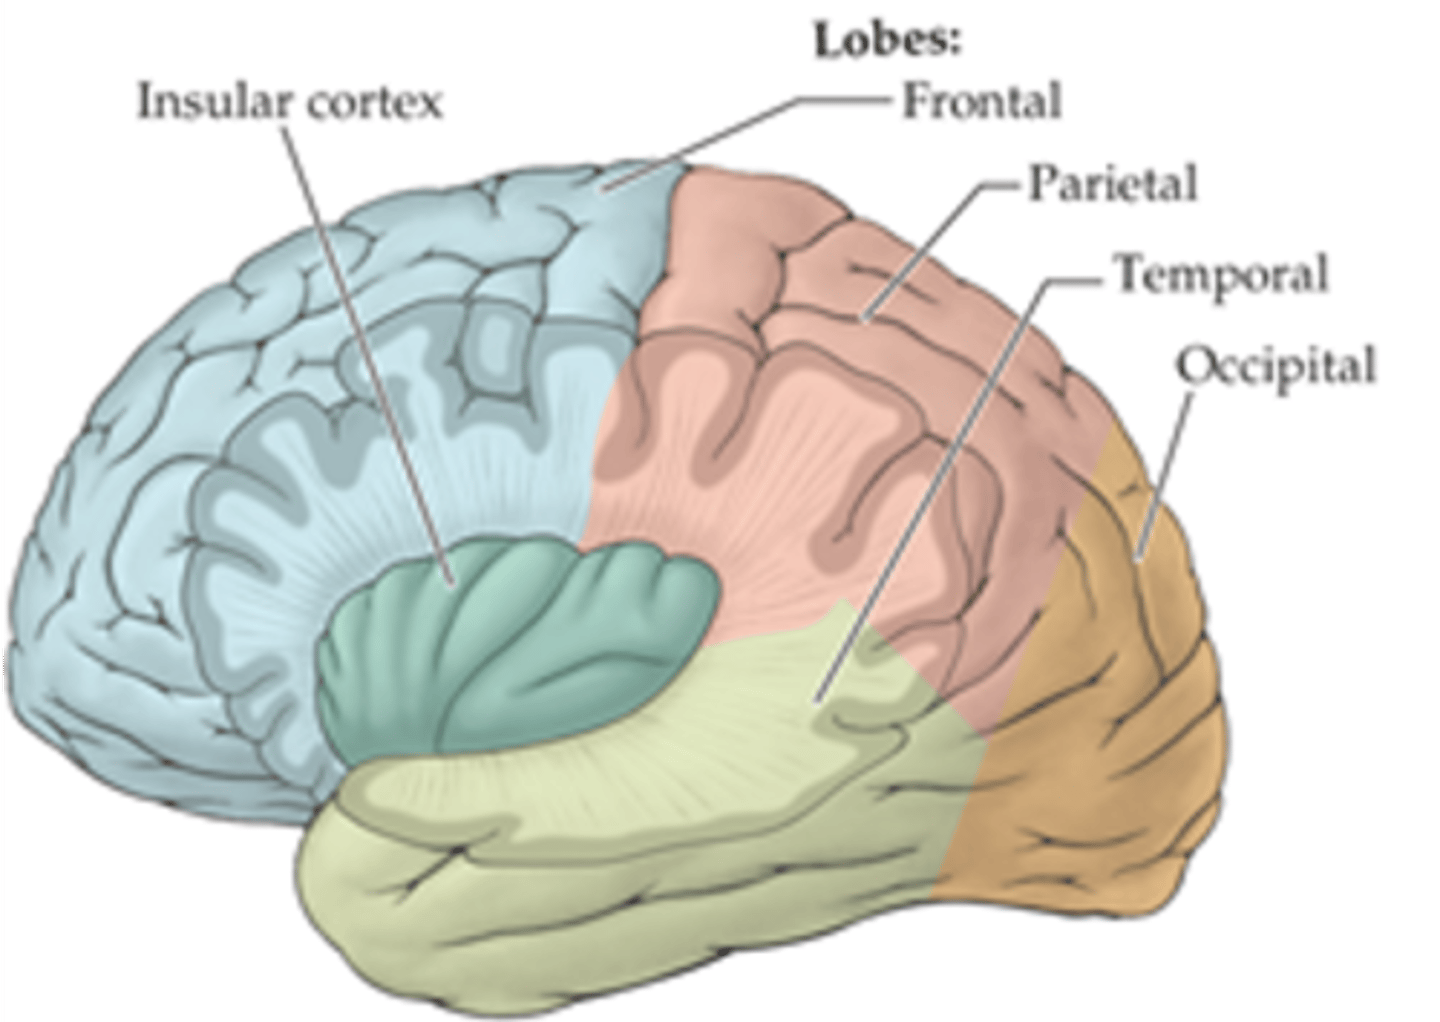

what are the 3 regions of the brain?

1. cerebrum (cerebral hemispheres)

2. brainstem

3. cerebellum

what are the 4 main lobes of the cerebrum?

FPOT

1. frontal

2. parietal

3. temporal

4. occipital

what additional lobe of the cerebrum is involved in receiving, processing, and integrating various types of information (taste, visceral sensation, pain, and balance)?

insula

additional lobe = insula and limbic lobe

what additional lobe of the cerebrum is involved in processing complex aspects of learning, memory, and emotion?

limbic lobe

additional lobe = insula and limbic lobe

which sulcus separates the cerebral hemispheres?

longitudinal fissure

which sulcus divides the frontal lobe from the parietal lobe and divides the precentral and postcentral gyrus?

central sulcus

which sulcus divides the parietal lobe from the temporal lobe?

lateral (sylvian) sulcus/fissure

which sulcus separates the parietal lobe from the occipital lobe?

parieto-occipital sulcus